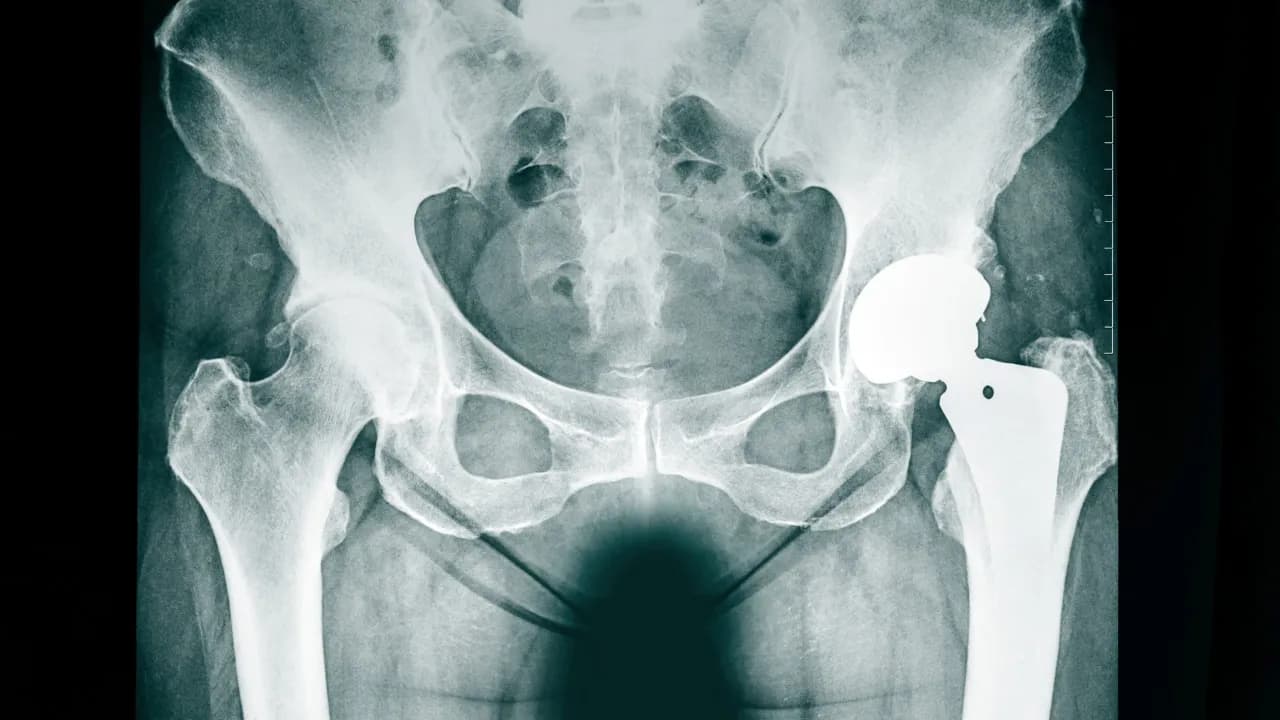

Jak rodzaj endoprotezy wpływa na odczuwany dyskomfort?

Rodzaj endoprotezy ma istotny wpływ na odczuwany dyskomfort po operacji. Endoprotezy cementowe oraz bezcementowe różnią się pod względem sposobu, w jaki są osadzone w kości, co może wpływać na poziom bólu. W przypadku endoprotez cementowych, które są osadzane w kości za pomocą specjalnego cementu, pacjenci często zgłaszają szybszą poprawę i mniejszy ból w porównaniu do implantów bezcementowych.

Endoprotezy bezcementowe, które są umieszczane w kości bez użycia cementu, mogą powodować dłuższy okres bólu, ponieważ wymagają czasu na zrośnięcie się z tkanką kostną. Pacjenci z endoprotezami bezcementowymi mogą odczuwać dyskomfort przez dłuższy czas, co jest istotne do rozważenia przy planowaniu zabiegu. Wybór odpowiedniego rodzaju endoprotezy powinien być dostosowany do indywidualnych potrzeb pacjenta oraz jego stanu zdrowia.